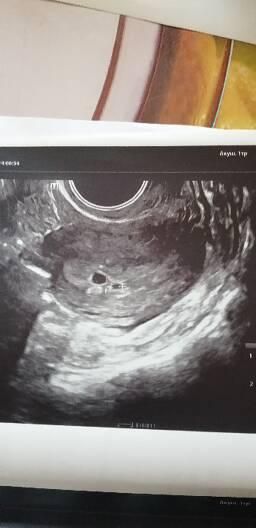

Моя история началась полтора месяца назад когда началась задержка, вот задержки 10 дней я уже обрадовалась но беременость не обнаружили, ни на узи н на хгч, прошло ещё 10 дней вот они 2 заветные полосочки, пошла к врачу такая вся радостная, мне сказали подозрение на внемат, пошла на узи обнаружили мою бусинку(1фото),но смутила большая задержка, подозрение уже было на замершую, пошла через 2 недели ещё раз узи, уже двойня оказалась и подтвердили замершую(2 фото), объясняла что может быть поздняя овуляция, но врачам на это.... Есть акурешский срок а он ему не соответствует,отправили на чистку.

На фото непонятно. За 2 недели плодное яицо должно было вырасти на 10-12 мм, и в нем д.б. виден эмбриончик. Повторите узи через недельку, или на хорошем аппарате.

Не ходите на чистку ! Прошу вас ! Сначала перепроверьте ! Меня тоже отправляли на чистку недавно ,у меня поздняя овуляция тоже ! Почитайте у меня в дневнике если интересно ! Подождите и переделайте УЗИ !у вас на первом УЗИ и на втором размер какой ПЯ? желточный мешочек есть ?

А какие размеры ПЯ на первом и на втором узи?